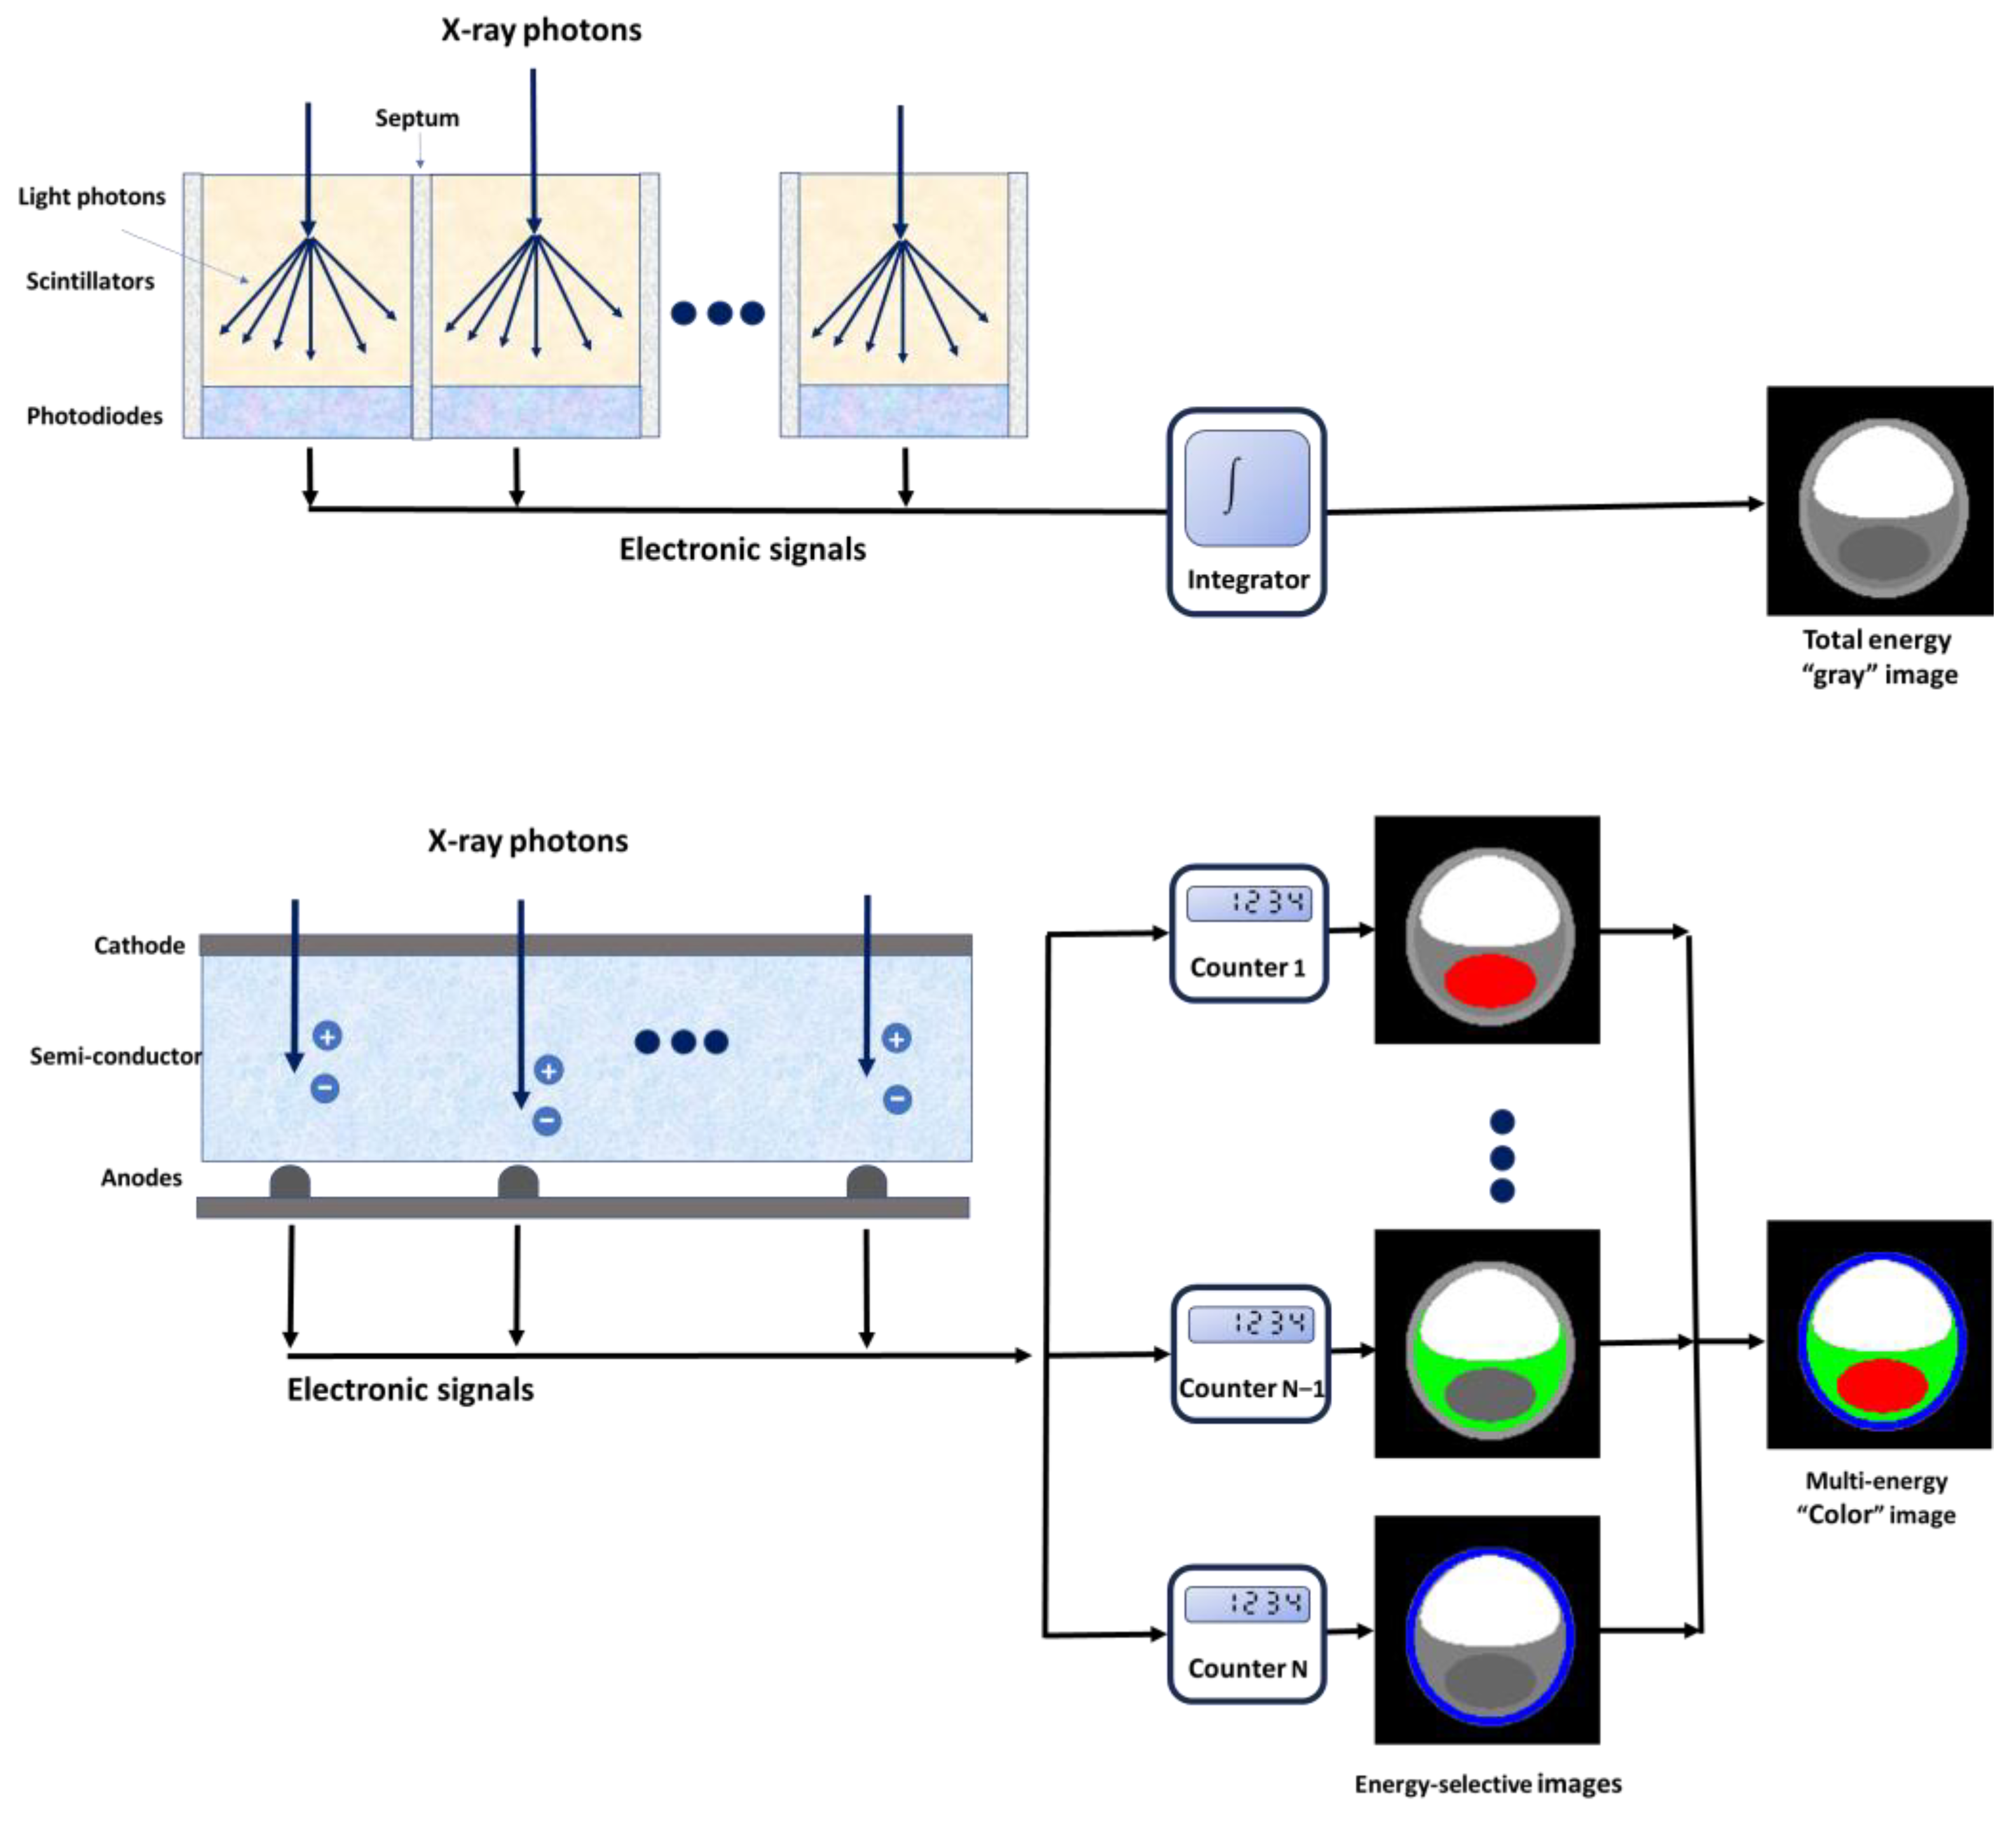

2. Spectral Photon-Counting CT Technology

2.1. Technical Aspects

2.2.2. Multi-Energy Acquisition